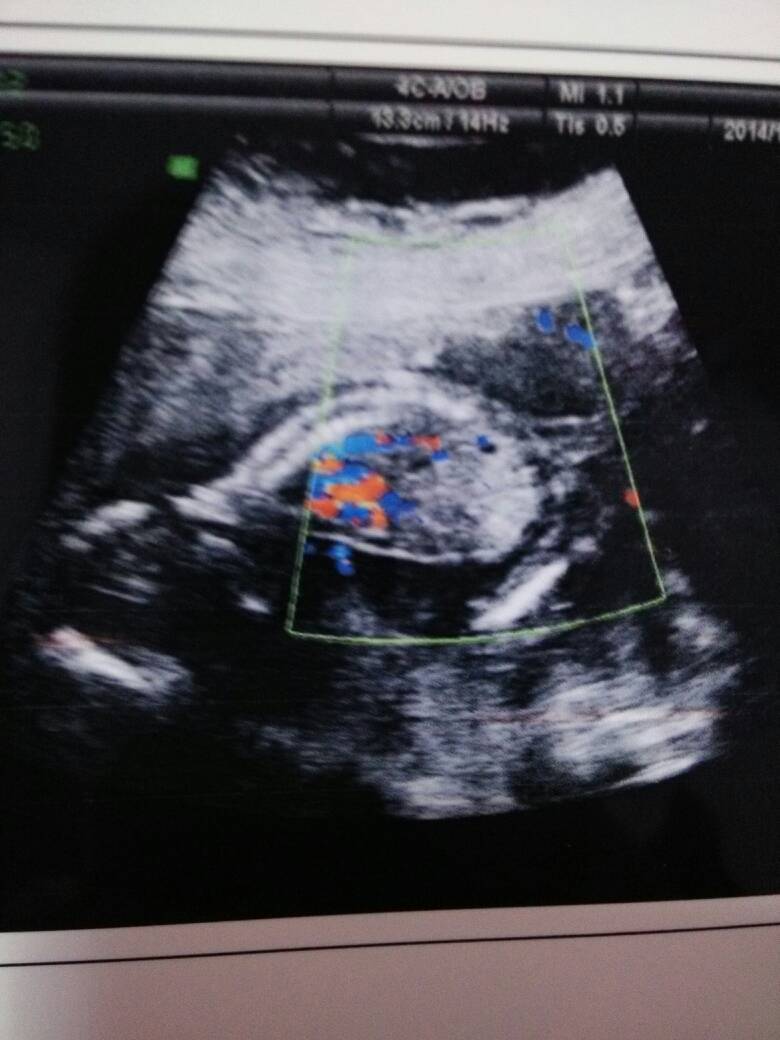

孕17周,图上的这些蓝色跟黄色的点点是什么? 点击展开 匿名用户 2014-11-23 20:32 为您推荐: 其他回答 应该是体内的器官还发育不成熟吧 匿名用户 2014-11-23 20:34 你可以咨询医师 匿名用户 2014-11-23 20:33 相关问题 孕10周刚才上厕所看见有淡黄色的东西这是怎么回事呢?是宝宝有什么嘛? 孕周38,最近老有黄色的分泌物是什么东东? 孕5周,白带承黄色是怎么回事?